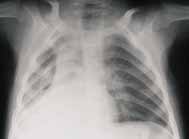

FIGURA 1. Proyección AP de tórax con neumonía viral en la cual existen infiltrados intersticiales parahiliares

radiados desde el hilio a la periferia en ambos parénquimas pulmonares.

Este tipo de infecciones comprometen principalmente la mucosa respiratoria y las vías aéreas, ocasionando inflamación y necrosis de las células ciliadas, células globosas y glándulas de la mucosa bronquial que llevan a edema de la pared bronquial y bronquiolar, que se manifiestan radiológicamente como opacidades peribronquiales, usualmente simétricas y radiadas de los hilios a la periferia (Figura 1).